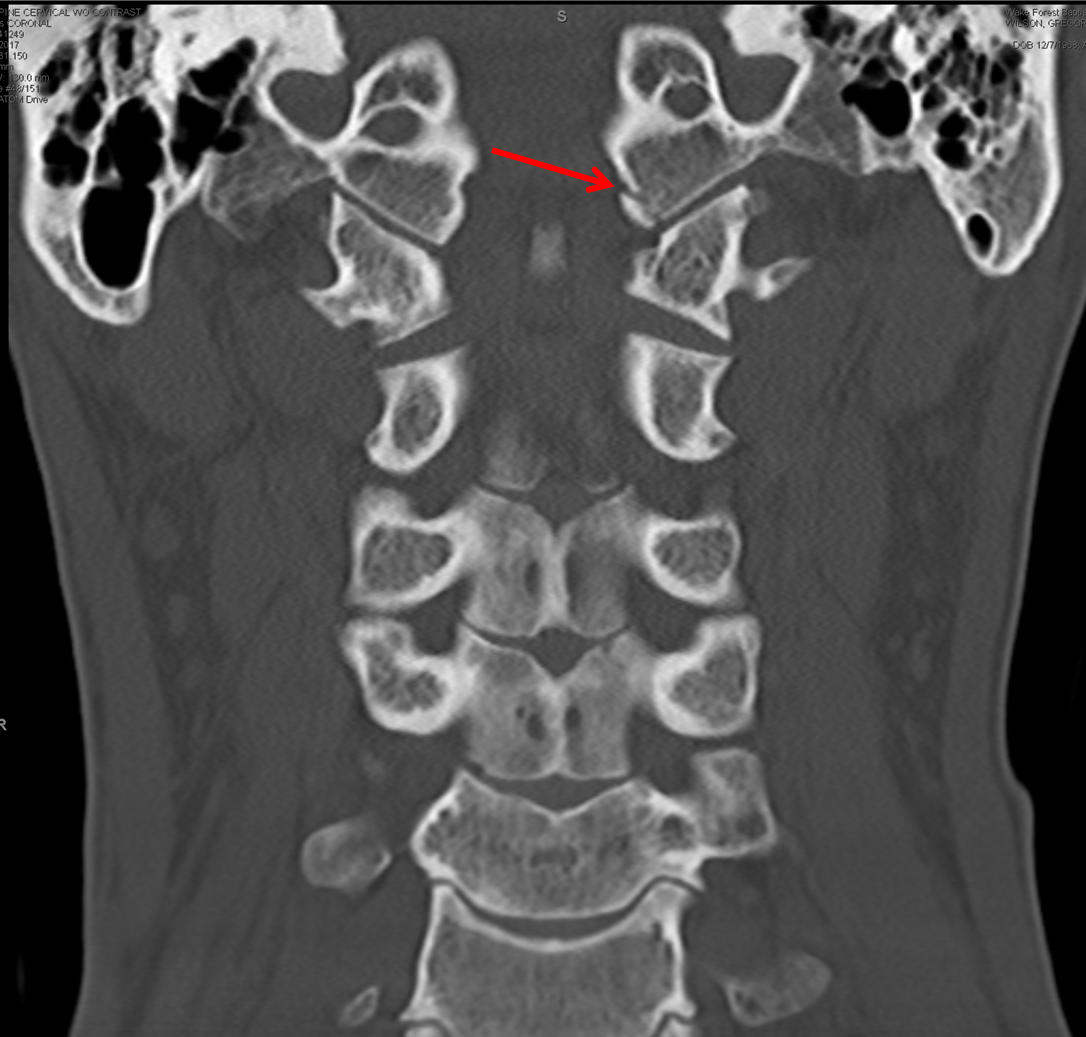

From radiologykey.com

Traumatic Injury of the Spine Radiology Key Crushing Injury Of The Occipital Bone    what injuries affect the cervical spine?  located at the back of the brain, the occipital lobes are responsible for visual perception. Sometimes, a broken skull bone can affect the brain.   basal skull fractures are most frequently diagnosed by clinical findings, making clinical assessment skills critical. The broken pieces of bone can cut into the. At times, patients. Crushing Injury Of The Occipital Bone.

Traumatic Injury of the Spine Radiology Key Crushing Injury Of The Occipital Bone    bullets can cause damage to brain parenchyma through 3 mechanisms:   basal skull fractures are most frequently diagnosed by clinical findings, making clinical assessment skills critical. Function of the occipital bone. Sometimes, a broken skull bone can affect the brain.   what injuries affect the cervical spine?   penetrating head trauma (pht) refers to any injury that breaches the. Crushing Injury Of The Occipital Bone.

Occipital condyle fracture on Spine CT Crushing Injury Of The Occipital Bone  At times, patients experience severe vision loss or total blindness. Sometimes, a broken skull bone can affect the brain. Damage to them results in loss of visual capability, an inability to identify colors, and hallucinations. Potential etiologies of on are wide and. The broken pieces of bone can cut into the. The occipital bone has many.   what injuries affect. Crushing Injury Of The Occipital Bone.